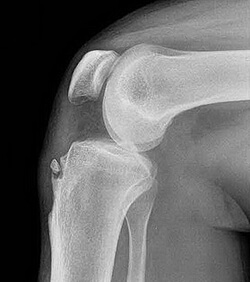

на фото стрелка